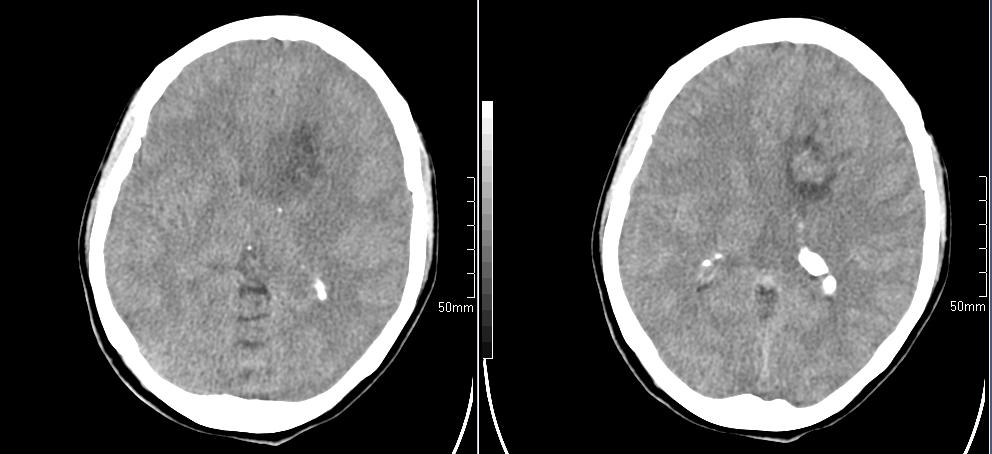

标题: CT23966:女,34岁,近一月头痛、意识障碍 [打印本页]

标题: CT23966:女,34岁,近一月头痛、意识障碍

左侧额叶见不规则软组织影,部分囊变,病变略呈等密度,占位效应明显,考虑血母可能。脑膜瘤不除外

左侧额叶肿瘤样病变,成等密度,其内可见囊变,肿瘤似与大脑镰相连,周围水肿不明显。考虑脑膜瘤可能!建议强化或mri。

左额叶囊实性肿块,实性部分呈等密度,密度不均,考虑胶质瘤可能性大,脑膜瘤及室管膜瘤不除外,建议mri增强扫描。

左额叶较大等低混杂密度影,占位效应明显,首先考虑:左额叶胶质瘤。